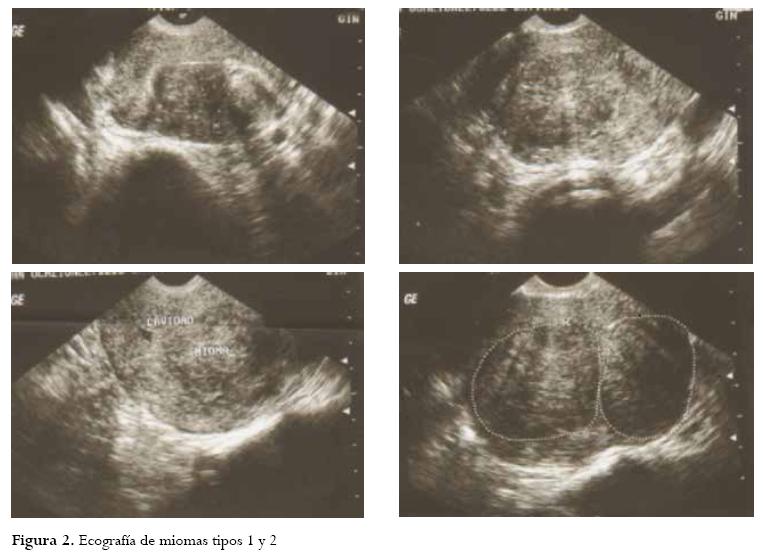

Paciente de 37 años, quien consulta en mayo de 2011 por infertilidad de un año de evolución y HUA de 4 meses de evolución a la Clínica SOMA, centro de alta complejidad, ubicado en Medellín, Colombia. Tenía antecedente de 2 miomectomías, la primera por laparoscopia y la segunda por laparotomía. Al examen físico se encuentra: útero fijo poco móvil retroverso que sugiere la presencia de un mioma en el segmento. La ecografía pélvica transvaginal reporta: 2 miomas intramurales con componente submucoso de 50 x 39 mm en cara anterior y otro fúndico de 48 x 25 mm (figura 2). Se realiza histeroscopia de consultorio el 26 de julio de 2011 para clasificar los miomas y decidir manejo histeroscópico frente a laparoscópico encontrando: 2 miomas submucosos tipos 1 y 2 de la clasificación FIGO; el primero, en la pared anterior, segmentario de 5 cm, el segundo localizado en la pared anterolateral izquierda de 5 cm.